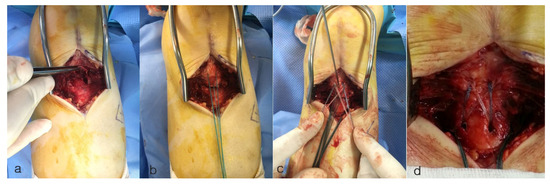

2. Case Presentation